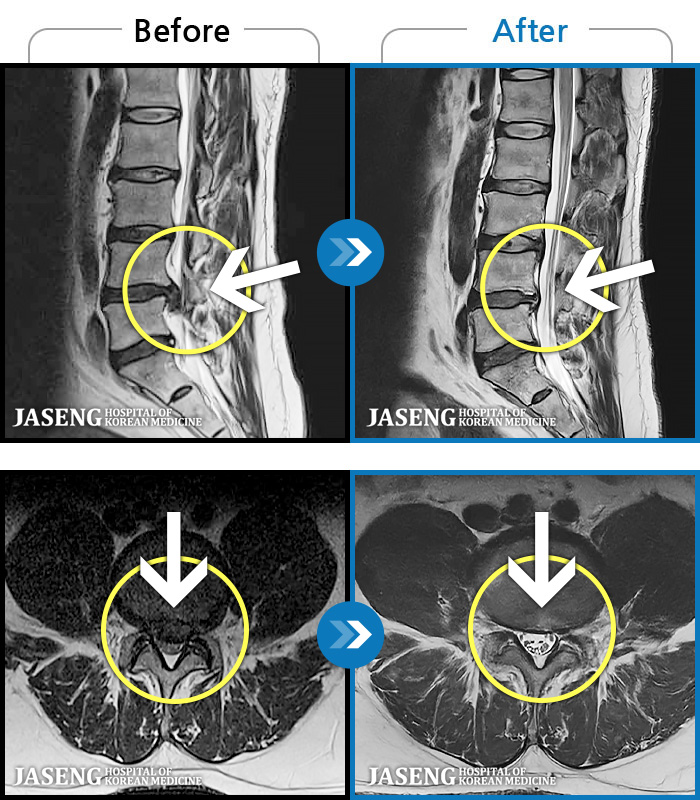

[Կñ:24.07.25~25.08.01]

[ϻ_㸮ũ] ݺ ӵǸ ڼ ÿ ȭǴ ߵ ̻ ȣϴ ¿ϴ.

No.1234

ȸ 253

2025.09.05